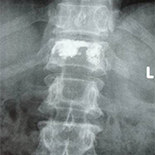

Patients (587 vertebral bodies) treated with percutaneous vertebroplasty or kyphoplasty in the Xi’an Honghui Hospital of Shanxi Province from January 2008 to January 2012 were retrospectively analyzed and 13 patients were enrolled in the study. These 13 patients had serious adverse events after percutaneous vertebroplasty or kyphoplasty. Their average age was 64.5 years old. Nine patients had spinal cord injury and 4 had nerve root injury. All the patients underwent open surgery within 4–12 h after definitive diagnosis.

All 13 cases were followed up (average time 14.1 months, range 3–47 months). Reasons for open surgery included cement extravasation (6 cases, 46.2%), puncture mistake (3 cases, 23.1%), and false selection of indications (4 cases, 30.8%). At last follow-up, skin feeling was better than that before open surgery in 4 cases with nerve root injury, and muscle strength recovered to grade 5 (3 cases) and grade 4 (1 case). In 9 cases with spinal cord injury, 7 patients improved and 2 remained at the same ASIA level.

The main reasons for open surgery after percutaneous vertebroplasty and kyphoplasty were cement extravasation (the most common reason), puncture mistake, and false selection of indications.